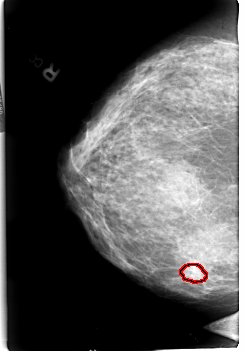

B_3009_1.RIGHT_CC

RIGHT_CC LINES 4552 PIXELS_PER_LINE 3160 BITS_PER_PIXEL 12 RESOLUTION 50 OVERLAY

FILE: B_3009_1.RIGHT_CC.OVERLAY

TOTAL_ABNORMALITIES 1

ABNORMALITY 1

LESION_TYPE CALCIFICATION TYPE AMORPHOUS-PLEOMORPHIC DISTRIBUTION CLUSTERED

ASSESSMENT 4

SUBTLETY 3

PATHOLOGY MALIGNANT

TOTAL_OUTLINES 1

BOUNDARY